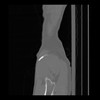

36 CUERPO,CE,Sagittal,3.000,CUERPO,Sagittal,